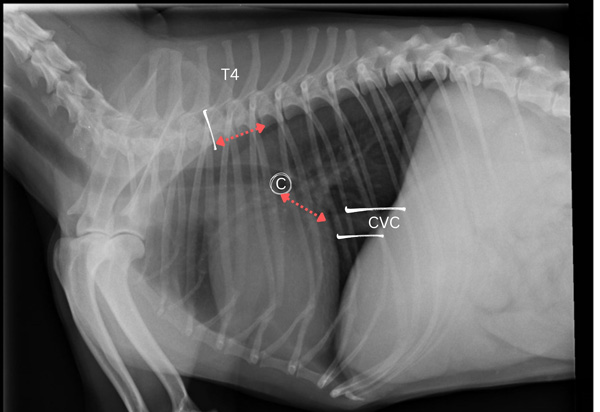

Figure 2: VHS. Lateral thoracic radiograph with carina (c), caudal vena cava (CVC), and spinous process of the fourth thoracic vertebra (T4) identified. Long axis of the cardiac silhouette (red line) is measured from carina to the apex of the heart and short axis (blue line) is measured from the cranial to the caudal border. These measurements are expressed in terms of vertebral body units using the cranial border of the fourth thoracic vertebra as the starting point.

Figure 3: VLAS. Lateral thoracic radiograph with carina (c), caudal vena cava (CVC), and spinous process of the fourth thoracic vertebra (T4) identified. Distance is measured from the carina to the dorsal border of the caudal vena cava at the site where it intersects the caudal aspect of the cardiac silhouette (red line). This measurement is expressed in terms of vertebral body units using the cranial border of the fourth thoracic vertebra as the starting point.

When echocardiography is not available and thoracic radiography is being used to evaluate heart size, a combination of vertebral heart score (VHS) and vertebral left aortic score (VLAS) should be used to reduce subjectivity. This involves measuring the distances between cardiac landmarks on a lateral thoracic radiograph and comparing these to the length of the patient’s thoracic vertebrae. When VHS and VLAS are being used, patients should meet all three of the criteria below to qualify as Stage B2.

To measure VHS:

- Obtain a good quality lateral thoracic radiograph centred over the heart.

- Identify the carina – a circular radiolucency dorsal to the base of the heart which corresponds to the bifurcation of the mainstem bronchi.

- Measure the long axis of the cardiac silhouette from the ventral border of the carina to the apex.

- Using the cranial border of the fourth thoracic vertebra as the starting point, express the length of the long axis of the cardiac silhouette in terms of vertebral body units (VBU) to the closest 0.1.

- Next, measure the short axis of the cardiac silhouette from the cranial border to the dorsal border at the widest part, perpendicular to the long axis.

- Express the length of the short axis in terms of VBUs, again using the cranial border of the fourth thoracic vertebra as the starting point.

- Add both numbers together to obtain the patient’s VHS10.

To measure VLAS:

- Use the same good quality lateral thoracic radiograph centred over the heart.

- Identify the caudal vena cava – a thick, soft-tissue opacity vessel running through the caudal thoracic cavity.

- Measure from the ventral aspect of the carina to the dorsal border of the caudal vena cava at the site where it intersects the caudal aspect of the cardiac silhouette.

- Express this distance in terms of VBUs, again using the cranial border of the fourth thoracic vertebra as the starting point11.